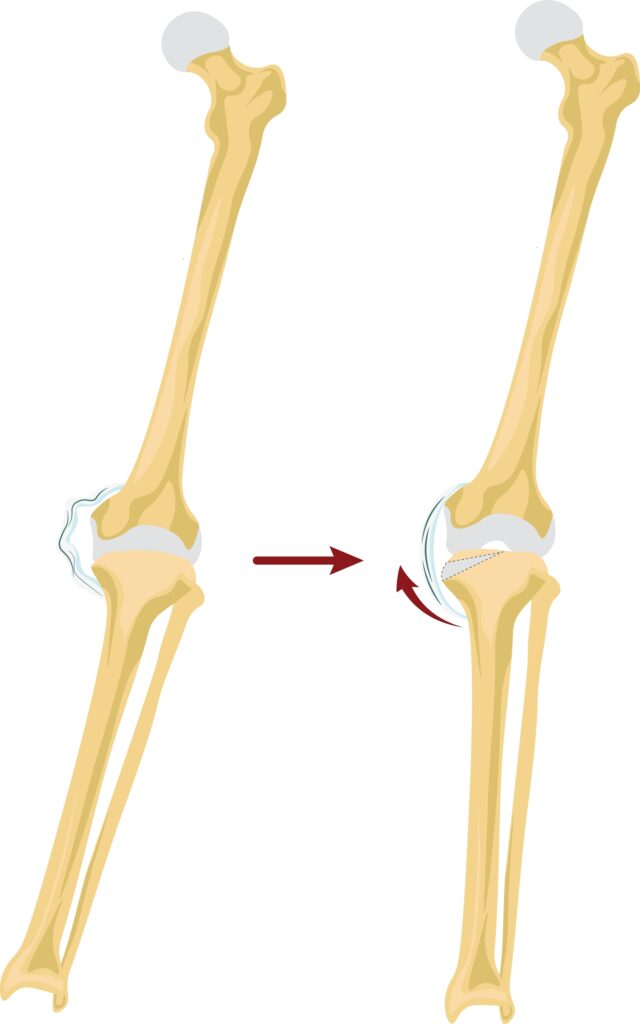

Osteotomia de tibie